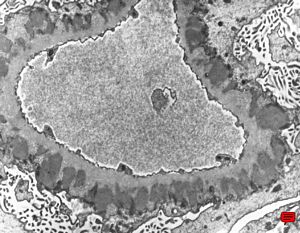

M,58y. | nephrotic syndrome: minimal changes - fusion of pedicles